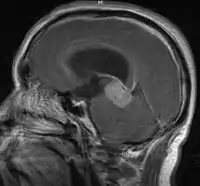

- Mainly located in midline structures, suprasellar region or pineal gland, also basal ganglia and hypothalamus

- Pineal Gland Germinoma

- Suprasellar Germinoma